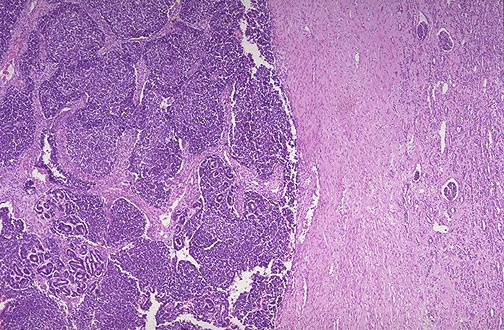

Image 4.2

At low power microscopically, most of the neoplasm is composed of small round blue cells (this is one of the small round blue cell tumors of childhood).